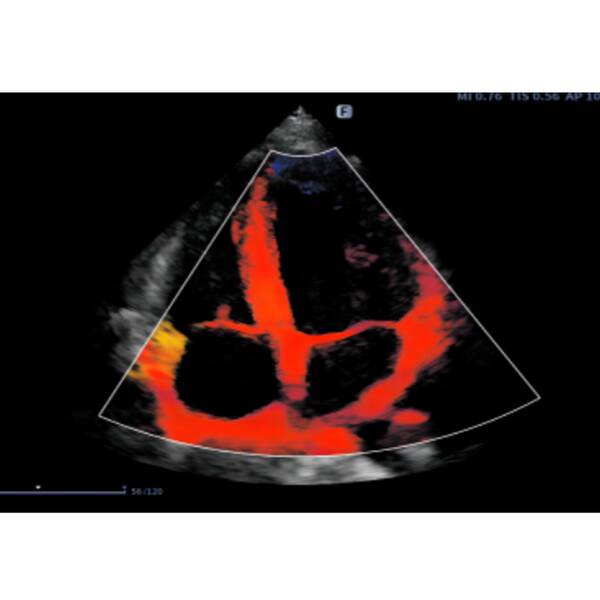

- Hi Platform — представляє абсолютно нову модернізовану платформу "HI" з інтелектуальним двоядерним процесором, що забезпечує надійну потужність паралельної обробки променів. Зображення з повним фокусуванням покращує чіткість кожної ділянки та забезпечує стабільну високу роздільну здатність. Технологія фазової візуалізації кровотоку використовує інформацію про час і просторові параметри для поліпшення захоплення сигналів низькошвидкісного кровотоку і рухомих тканин, ефективно пригнічує перешкоди сигналу, не пов'язаного з кровотоком.